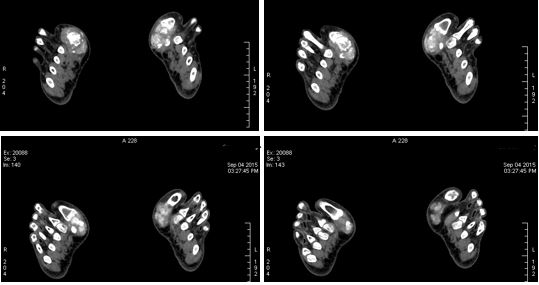

双足内多发关节痛风结节沉积;双侧第一近侧趾趾关节最为显著;痛风VR渲染为绿色结节。

70keV单能灰阶图像

70keV单能图像:关节周围痛风结节沉积密度并不均匀,可以侵犯骨质,并夹杂着散在钙化。